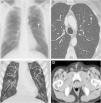

We describe the imaging findings of a 64-year-old patient with a past medical history of a moderately differentiated early stage prostate cancer that was successfully treated 3 years earlier with brachytherapy seeds. The patient, who was a former smoker, complained of cough and dyspnea. A chest radiograph did not show nodules or signs of pneumonia, but incidentally revealed a small intrapulmonary metallic density in the left lung (Fig. 1A). Thoracic computed tomograpy (CT) confirmed a single migrated brachytherapy seed within a small subsegmental pulmonary artery of the left upper lobe (Fig. 1B and C). Abdominal CT ruled out other migrated brachytherapy seeds (Fig. 1D). The patient's respiratory picture rapidly improved and the decision was to follow up the patient by his primary care provider.

(A) Posteroanterior chest radiograph shows a small metallic density in the left lung (arrow). (B) and (C) Axial (B) and coronal MIP (maximum intensity projection), (C) CT images (lung window) confirm that the metallic density corresponds to a single migrated brachytherapy seed in the left upper lobe (arrow). (D) Axial CT image at the level of the pelvis shows multiple brachytherapy seeds within the prostate.